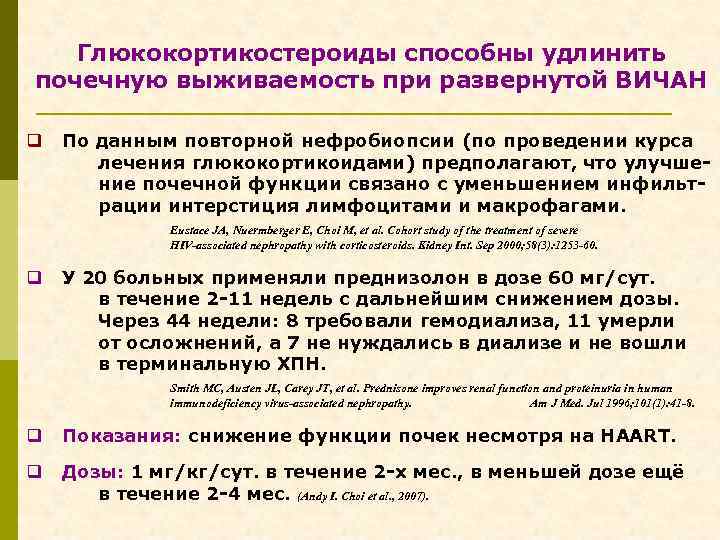

Глюкокортикостероиды способны удлинить почечную выживаемость при развернутой ВИЧАН q По данным повторной нефробиопсии (по проведении курса лечения глюкокортикоидами) предполагают, что улучшение почечной функции связано с уменьшением инфильтрации интерстиция лимфоцитами и макрофагами. Eustace JA, Nuermberger E, Choi M, et al. Cohort study of the treatment of severe HIV-associated nephropathy with corticosteroids. Kidney Int. Sep 2000; 58(3): 1253 -60. q У 20 больных применяли преднизолон в дозе 60 мг/сут. в течение 2 -11 недель с дальнейшим снижением дозы. Через 44 недели: 8 требовали гемодиализа, 11 умерли от осложнений, а 7 не нуждались в диализе и не вошли в терминальную ХПН. Smith MC, Austen JL, Carey JT, et al. Prednisone improves renal function and proteinuria in human immunodeficiency virus-associated nephropathy. Am J Med. Jul 1996; 101(1): 41 -8. q Показания: снижение функции почек несмотря на HAART. q Дозы: 1 мг/кг/сут. в течение 2 -х мес. , в меньшей дозе ещё в течение 2 -4 мес. (Andy I. Choi et al. , 2007).